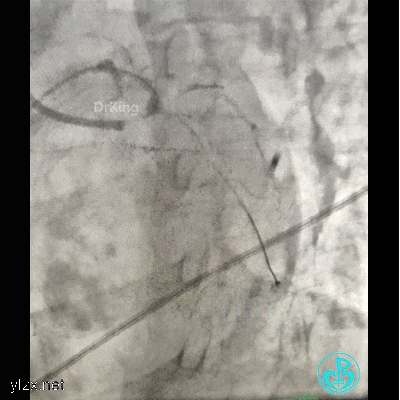

植入4.0×13mm支架1枚。

交换导丝后扩支架网眼。

结束手术。

下台时血压127/78mmHg,心率75次/分。